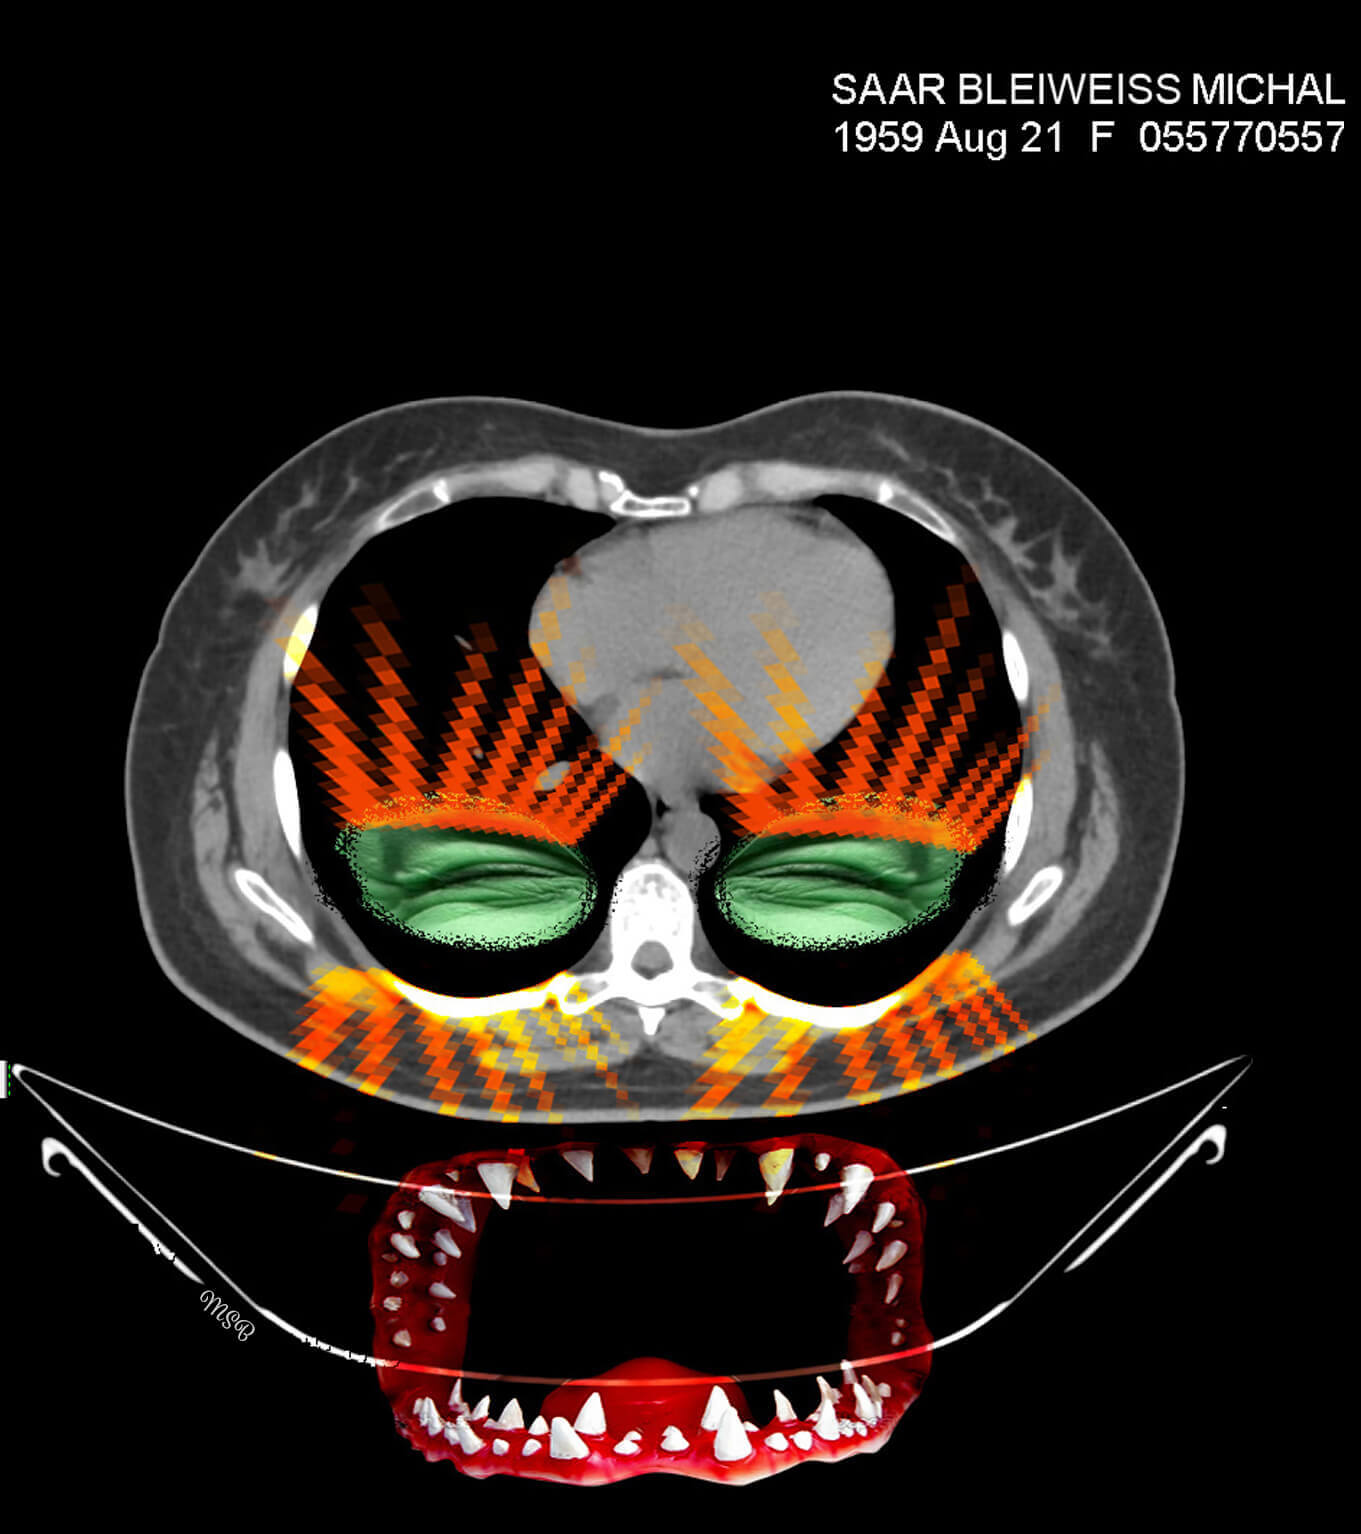

A reimagining of “self,” by Michal Saar-Bleiweiss

The images before me were entirely in black and white, devoid of personality or character. There was no sign of the Michal that was me, and I felt a great desire and need to take these images to reinstate Michal, the person. When we returned home, I was curious about how I would feel when I looked at the images again—but this time on my computer screen. What I saw created an emotional storm within me.

This storm opened my “third eye,” enabling me to look inside myself. In my imagination I saw colors, dimensions, and expressive features, such as eyes. This was probably my way of internalizing my new reality, digesting what is going on inside me and brushing off my fears and pain. I wanted and needed to wake up each morning with a new smile and the ability to cope.

One of the few people I did share it with was a medical professor, who is also an artist in his own right. He introduced me to Harmony software, a simple drawing software program that enables the user to scribble and draw (primarily in black and white) with several types of brushes.

Having released the pain from the CT images, I found myself opening the next chapter in my imagination—creating digital collages.